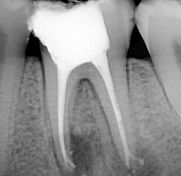

Il paziente di 17 anni si presenta all'osservazione con un ascesso odontogeno, sostenuto dall'elemento 36 necrotico per carie destruente; all'rx iniziale sono apprezzabili lesioni periapicali su entrambe le radici.

La terapia canalare è stata effettuata in monoseduta; per la sagomatura sono stati utilizzati strumenti ProTaper sino a diametro 25 (strumento F2); a questa è seguita una accurata fase di detersione con ipoclorito, attivato mediante ultrasuoni, e la chiusura con sistema Thermafil. Particolarmente interessante è notare come la scomposizione laterale della forza durante l'inserimento del cono di guttaperca abbia determinato un buon riempimento del delta sulla radice mesiale e un sigillo sulla radice distale, con anatomia di tipo Weine IV.